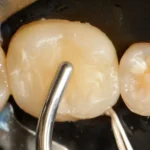

Confira este caso clínico de restauração dentária posterior, terceiro molar, com a resina tipo Bulk da 3M.

Passo a passo de como remover restauração de amálgama